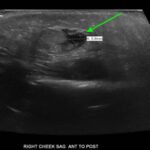

Rhabdomyolysis is a potentially life-threatening disease defined by the release of intracellular contents into the body’s circulation after muscle damage. It is most commonly seen in adult patients who present with crush injuries, overexertion, or prolonged immobility due to drug and/or alcohol overdose. Fortunately, it is rare in young children. We present the case of an 8-month-old girl with progressively worsening right-sided facial swelling that was associated with significant drooling and intraoral edema. The patient had been found lying prone and wedged between a mattress and the adjacent bedroom wall. After laboratory and imaging work-up, this child’s injury was the result of prolonged facial muscle compression with resultant rhabdomyolysis. The patient improved during hospital admission with intravenous (IV) fluids, two days of steroids for facial swelling, and five days of antibiotics to treat superficial cellulitis. At 2-week follow-up, her swelling resolved with minimal residual facial scarring and a mild right facial nerve palsy. This patient’s unusual history and clinical presentation challenges providers to explore rhabdomyolysis as a differential diagnosis in young children who present with localized severe swelling.